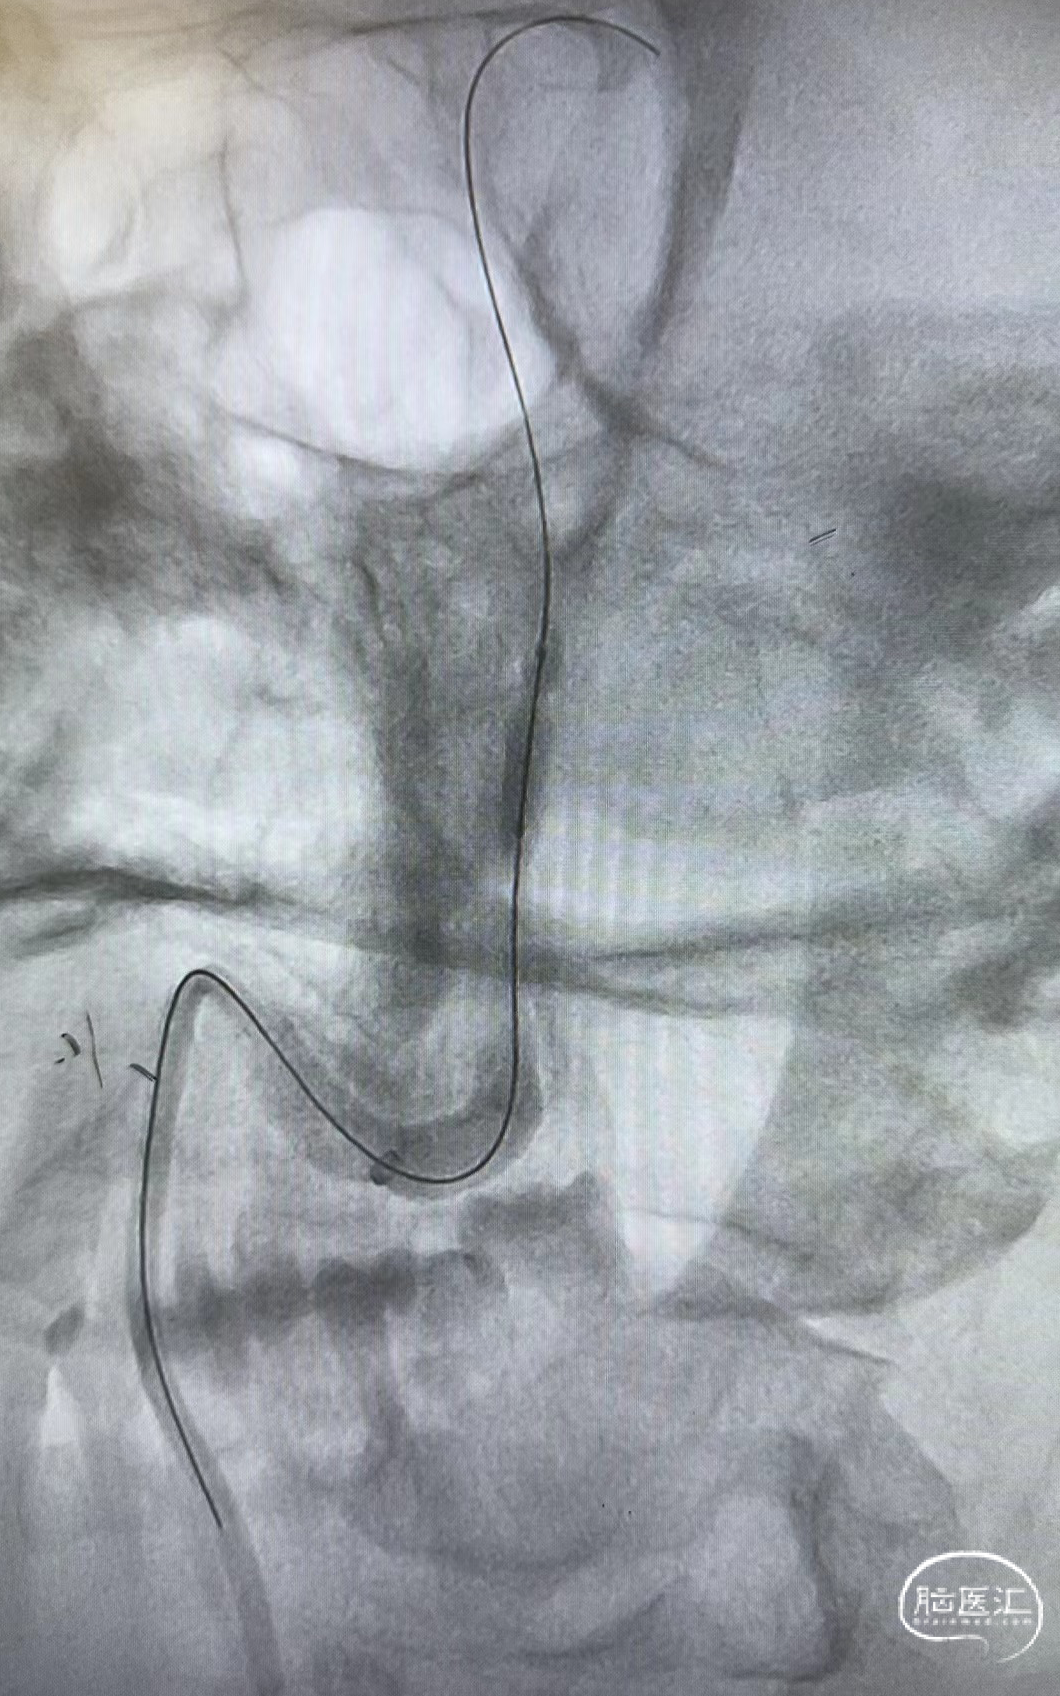

操作入路

股动脉穿刺

微导丝:Synchro 0.014inch*200cm

中间导管:6F 115cm远端通路导管